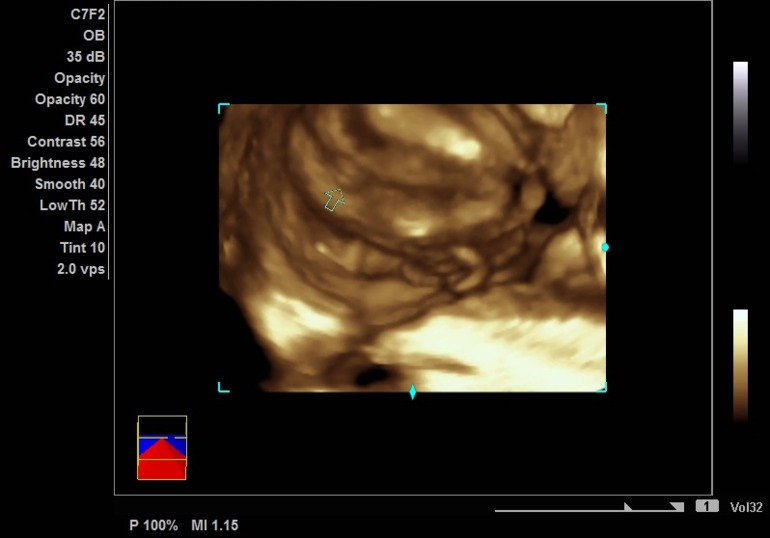

Узи может быть ошибочным

Узи может быть ошибочным 113 фотографий